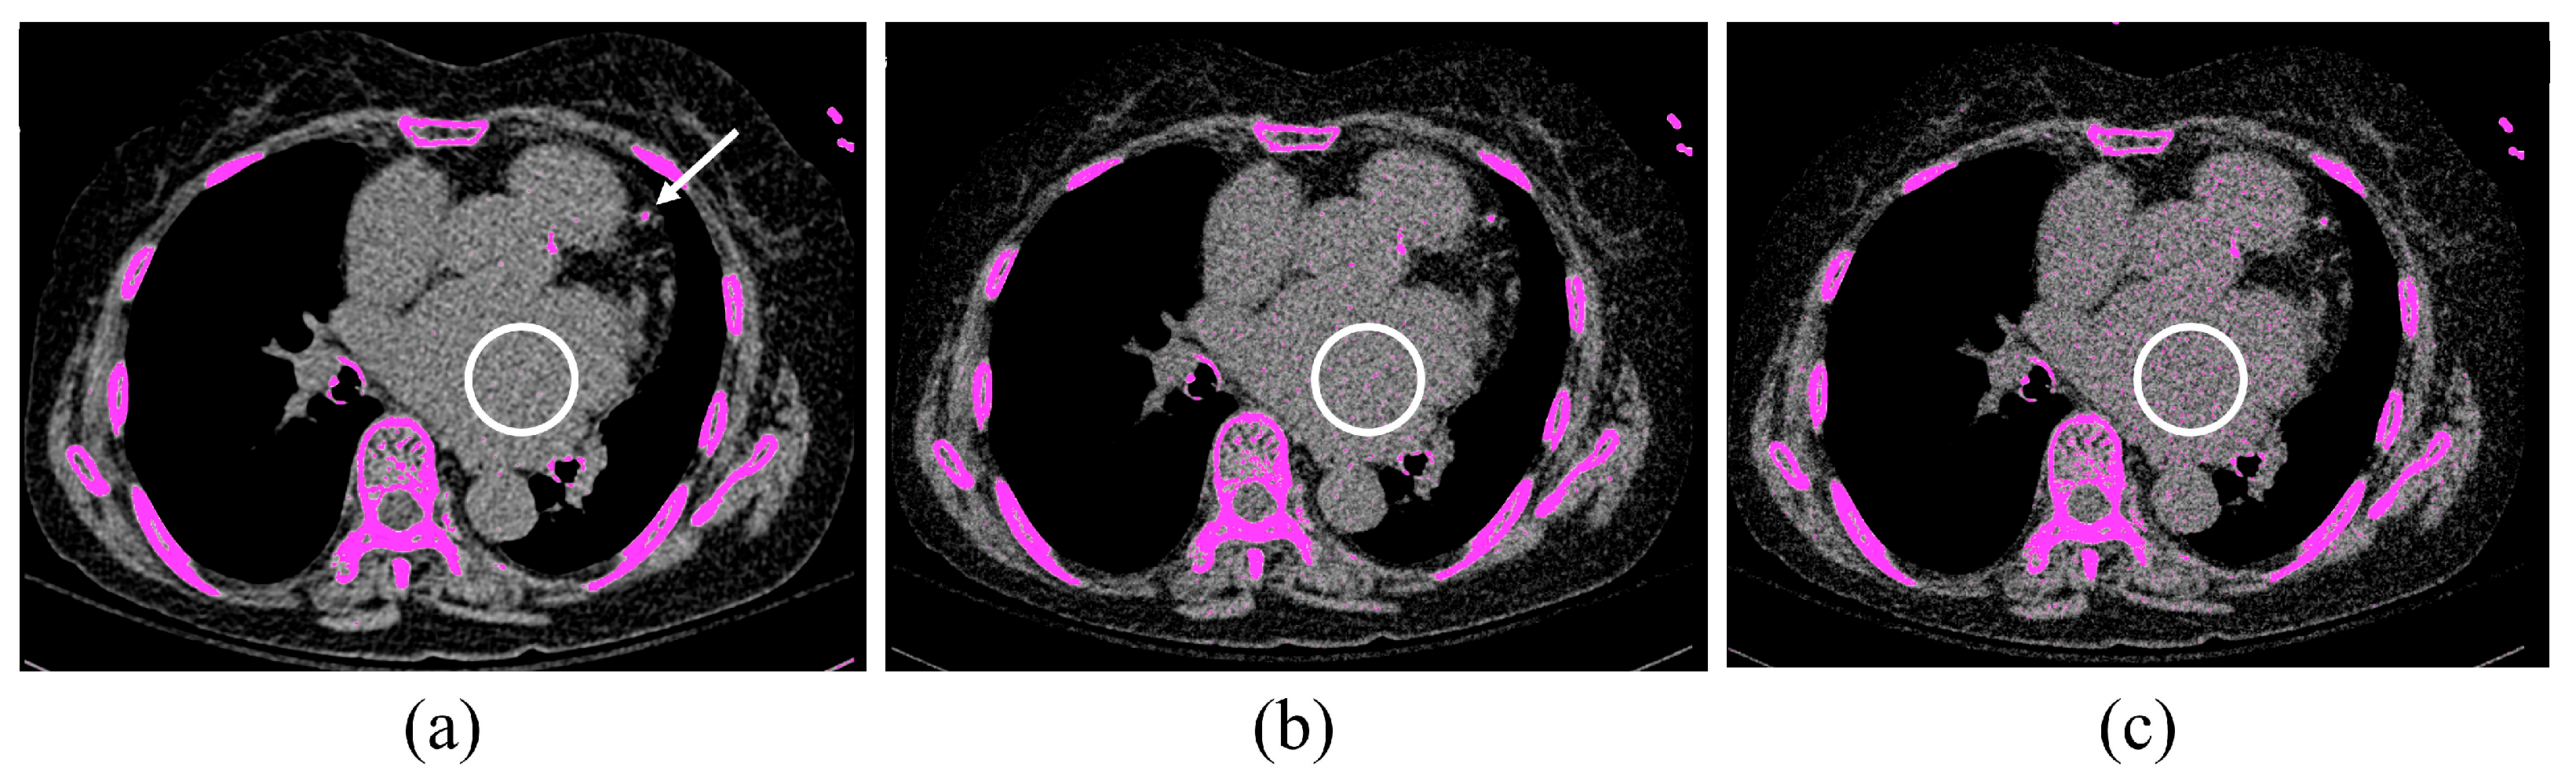

3. Results

3.1. Patient Study

3.2. Phantom Study

4. Discussion